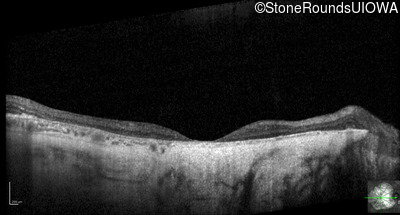

Visit at age: 76 years (Visit 2)

Optical Coherence Tomography - Right - 10/160 sc

Exemplar / OCT Stack